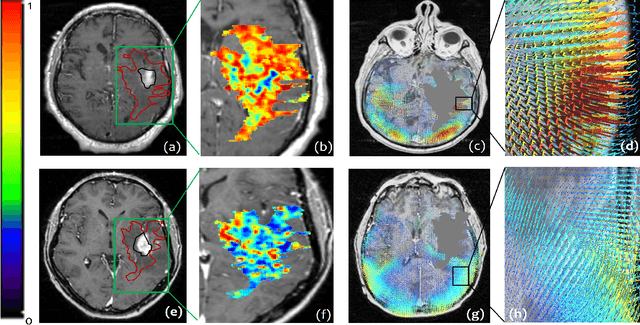

Abstract:The concept of tumor field effect implies that cancer is a systemic disease with its impact way beyond the visible tumor confines. For instance, in Glioblastoma (GBM), an aggressive brain tumor, the increase in intracranial pressure due to tumor burden often leads to brain herniation and poor outcomes. Our work is based on the rationale that highly aggressive tumors tend to grow uncontrollably, leading to pronounced biomechanical tissue deformations in the normal parenchyma, which when combined with local morphological differences in the tumor confines on MRI scans, will comprehensively capture tumor field effect. Specifically, we present an integrated MRI-based descriptor, radiomic-Deformation and Textural Heterogeneity (r-DepTH). This descriptor comprises measurements of the subtle perturbations in tissue deformations throughout the surrounding normal parenchyma due to mass effect. This involves non-rigidly aligning the patients MRI scans to a healthy atlas via diffeomorphic registration. The resulting inverse mapping is used to obtain the deformation field magnitudes in the normal parenchyma. These measurements are then combined with a 3D texture descriptor, Co-occurrence of Local Anisotropic Gradient Orientations (COLLAGE), which captures the morphological heterogeneity within the tumor confines, on MRI scans. R-DepTH, on N = 207 GBM cases (training set (St) = 128, testing set (Sv) = 79), demonstrated improved prognosis of overall survival by categorizing patients into low- (prolonged survival) and high-risk (poor survival) groups (on St, p-value = 0.0000035, and on Sv, p-value = 0.0024). R-DepTH descriptor may serve as a comprehensive MRI-based prognostic marker of disease aggressiveness and survival in solid tumors.

Abstract:With growing emphasis on personalized cancer-therapies,radiogenomics has shown promise in identifying target tumor mutational status on routine imaging (i.e. MRI) scans. These approaches fall into 2 categories: (1) deep-learning/radiomics (context-based), using image features from the entire tumor to identify the gene mutation status, or (2) atlas (spatial)-based to obtain likelihood of gene mutation status based on population statistics. While many genes (i.e. EGFR, MGMT) are spatially variant, a significant challenge in reliable assessment of gene mutation status on imaging has been the lack of available co-localized ground truth for training the models. We present Spatial-And-Context aware (SpACe) "virtual biopsy" maps that incorporate context-features from co-localized biopsy site along with spatial-priors from population atlases, within a Least Absolute Shrinkage and Selection Operator (LASSO) regression model, to obtain a per-voxel probability of the presence of a mutation status (M+ vs M-). We then use probabilistic pair-wise Markov model to improve the voxel-wise prediction probability. We evaluate the efficacy of SpACe maps on MRI scans with co-localized ground truth obtained from corresponding biopsy, to predict the mutation status of 2 driver genes in Glioblastoma: (1) EGFR (n=91), and (2) MGMT (n=81). When compared against deep-learning (DL) and radiomic models, SpACe maps obtained training and testing accuracies of 90% (n=71) and 90.48% (n=21) in identifying EGFR amplification status,compared to 80% and 71.4% via radiomics, and 74.28% and 65.5% via DL. For MGMT status, training and testing accuracies using SpACe were 88.3% (n=61) and 71.5% (n=20), compared to 52.4% and 66.7% using radiomics,and 79.3% and 68.4% using DL. Following validation,SpACe maps could provide surgical navigation to improve localization of sampling sites for targeting of specific driver genes in cancer.